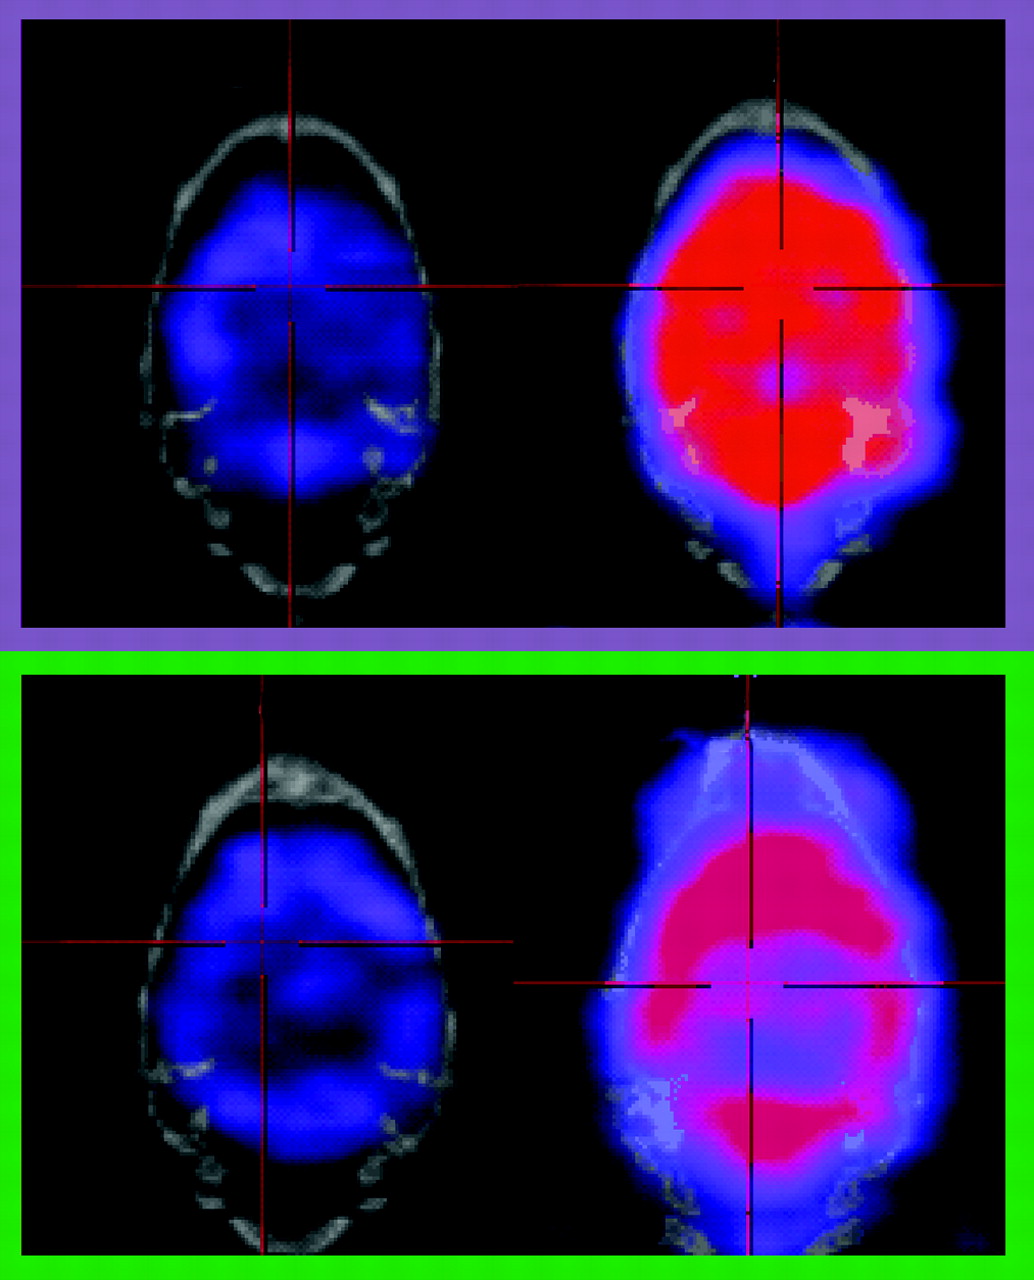

Drug-induced changes in cerebral blood flow evaluated by split-dose SPECT. In the split-dose SPECT study, rats were infused with a first dose of 99mTc-HMAPO at 1 mCi followed by a second dose at 2 mCi; changes in blood flow were then elicited by saline (n=3) or acetazolamide at 30mg/kg iv (n=3). Based on the images acquired from the pre-drug and post-drug periods, mean R-values (indicator of relative drug-induced change in cerebral blood flow) were calculated from specific regions of interest. Our results indicated that, compared to saline-treated rats, ACZ-treated rats show changes in prefrontal cortex (PFC) and cerebellum that reflect the known vasodilatation effect of ACZ. This imaging technique has been widely used in humans, and thus it can serve as a useful translational tool for drug discovery.